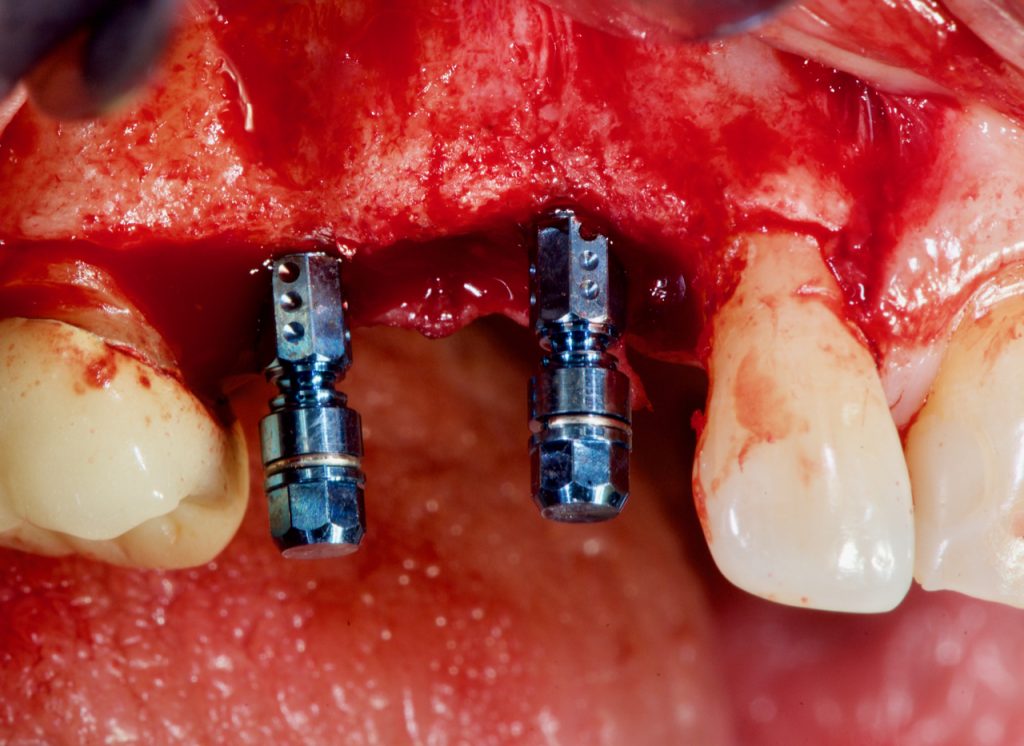

Posición Mesiodistal.

Es obligatorio mantener una distancia de 1,5 mm entre el implante y los dientes adyacentes (Tarnow 2000).

Esta distancia protegerá el pico óseo interproximal de ser afectado por la pérdida de hueso marginal que tiene lugar cuando se forma el espacio biológico.

La reacción inflamatoria que tiene lugar alrededor del gap entre el implante y el tornillo de cicatrización ó entre el implante y el pilar, produce una respuesta inflamatoria que produce una pérdida ósea marginal de 1.5 mm (Berglundh 1991, Ericsson 1995).

Si esta pérdida ósea marginal afecta el pico óseo interproximal, este se reabsorberá y la presencia de la papila, entre la rehabilitación protésica y los dientes, será cuanto menos improbable.

Esta regla también se aplica a los implantes en los que se debe mantener una distancia de 3 mm para evitar la confluencia de la pérdida ósea marginal de los dos implantes, lo que provocaría el colapso de la papila interproximal (Tarnow 2001).

Existen algunas herramientas que pueden ayudar a evitar la colocación de implantes demasiado cerca a un diente u otro implante.

Esta es una herramienta de las herramientas que podemos utilizar para evitar colocar el implante en una posición comprometida.

Posición mesiodistal: el implante debe colocarse a 1,5 mm de distancia de los dientes adyacentes. Si es posible, debe colocarse a 2 mm de distancia para evitar que la pérdida ósea marginal afecte el pico óseo interproximal.

La distancia entre los implantes debe ser de 3 mm, aunque algunos autores declararon que los implantes con Platform Switching podrían colocarse hasta una distancia de 2 mm (Ciurana 2009).